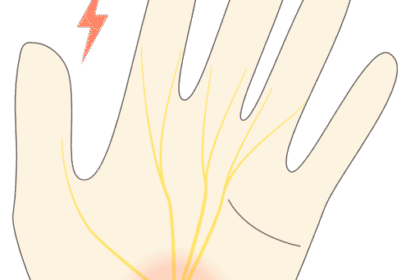

小指側にある尺骨神経が手首の尺骨神経管(ギヨン管)の中で

締め付けられたり、圧迫を受けると尺骨神経沿いに症状があらわれます

⭕️の位置が尺骨神経の通り道です

この部分が圧迫を受けると腱鞘炎になります

写真のように小指と薬指半分が痺れたり痛みがでます

これは尺骨神経が支配している範囲です